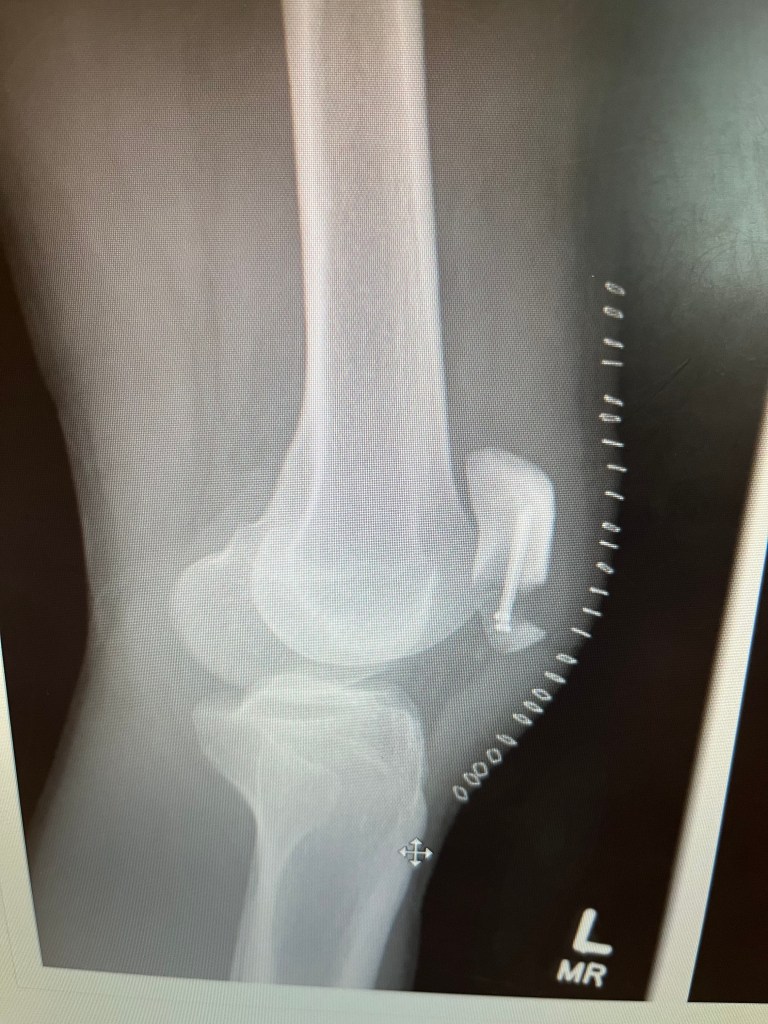

Wow. Hello again readers of the blog. It’s been almost two weeks since my last update, and I want to acknowledge my longer-than-intended break. As per my last post, I had my follow up appointment on the seventh of May. At my follow up appointment, they found out that my bone did not heal correctly even with the screws put in.

Of course, I saw this before I got told anything at my follow up appointment. The radiology technician opened the X-rays for my doctor to see, and he left it on this one for a split second and clicked off. Then left the room. Leaving me, puzzled and anxious for my doctor’s arrival, knowing that another surgery is coming. I couldn’t help but cry in the office when he officially told me he recommends another surgery the next day. Ultimately, I had no choice but to go with it. Without it, my strength and mobility would never be the same. I feel that I chose a fairly difficult route, as that meant the last two and a half weeks had been for nothing.

The surgery details are messed up; this recovery has been way harder because of what they had to do, and my body already being through so much. My surgeon removed the smaller piece of my kneecap that didn’t heal onto the rest of my kneecap. So, he went the tendon route: he stitched my tendons to the rest of my bone through tiny holes in it, so the tendons can heal onto that larger piece of my bone. He still expects me to make a full recovery, which is good, but this is probably the easiest part of recovery I’ve been through. Up until a week after my surgery, I have been in constant pain, and doing things got physically harder. Even when I was hanging out with people or at home, I would be laying down or sitting down. Although I think this second surgery will be worth it in the end, it is going to be very difficult to get to that end: if there will ever be one.